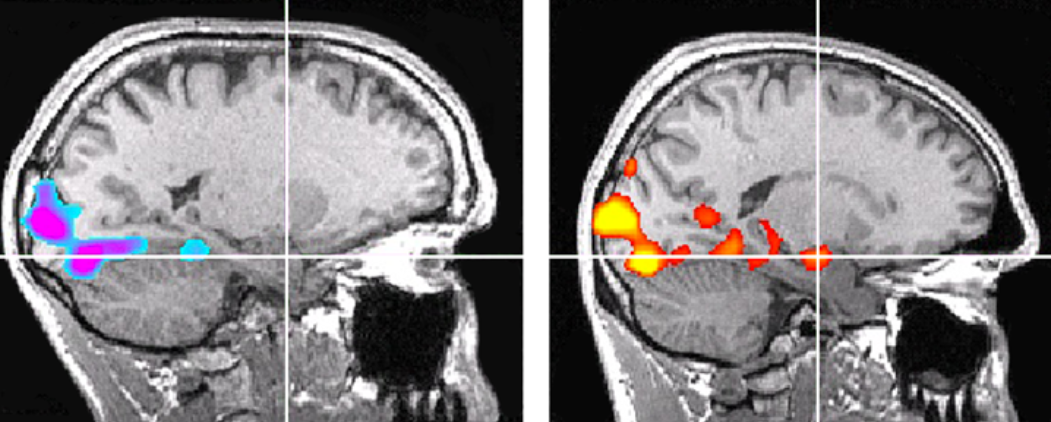

Ngay cả với người không chuyên, lý do khiến Joseph quan tâm cũng khá rõ. Joseph dùng một đối chứng: một vận động viên leo núi nam cùng độ tuổi, cũng là người tìm kiếm cảm giác mạnh. Giống Honnold, người này mô tả các nhiệm vụ trong máy quét là cực kỳ nhạt nhẽo. Thế nhưng trên ảnh fMRI phản ứng với các hình ảnh kích thích mạnh, vùng hạch hạnh nhân của đối chứng sáng rực màu tím điện, như biển quảng cáo neon. Còn của Honnold thì xám xịt. Không có chút hoạt động nào.

Ảnh quét so sánh não bộ của Honnold (trái) với một đối chứng (phải). Dấu chữ thập chỉ hạch hạnh nhân, một nhóm nhân não liên quan tới việc tạo ra phản ứng sợ hãi. Khi cả hai cùng nhìn vào những hình ảnh kích thích giống nhau, hạch hạnh nhân của đối chứng phát sáng, trong khi của Honnold vẫn trơ lì, hoàn toàn không có hoạt động. Ảnh: Jane Joseph

Chuyển sang ảnh của bài kiểm tra phần thưởng bằng tiền: một lần nữa, hạch hạnh nhân và nhiều vùng não khác của đối chứng “sáng lên như cây thông Noel”, theo lời Joseph. Trong não Honnold, hoạt động duy nhất nằm ở các vùng xử lý thị giác chỉ xác nhận rằng anh vẫn tỉnh và đang nhìn màn hình. Phần còn lại của não là đen trắng, tĩnh lặng.

Để chắc rằng mình không bỏ sót điều gì, Joseph đã hạ thấp ngưỡng thống kê. Cuối cùng bà tìm được đúng một voxel (đơn vị thể tích não nhỏ nhất mà máy quét ghi nhận) sáng lên ở hạch hạnh nhân. Nhưng ở mức đó, dữ liệu thật không thể phân biệt với sai số. “Ở bất kỳ ngưỡng hợp lý nào, cũng không có hoạt động của hạch hạnh nhân”, bà nói.